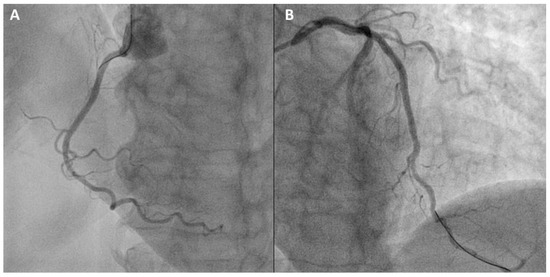

2. Case Vignette